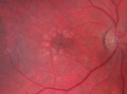

52 year old HIV negative man. May of 2014 the right eye had a vitrectomy for a floater. He was told that the doctor couldn't get all the floaters. He had cataract surgery (required 2 surgeries for the cataract). Them a different retina docotor then did another vitrectomy and scraped the scar tissue off the retina which had formed because the initial doctor couldn't get everything. The patient gave up a few months ago. He cannot see out of the right eye. There is constant flickering and distorted vision in the right eye. Since he stopped treatment his vision is no worse. He sees a fog out of the right eye and light and dark. 6/12/14 no pucker. The retina specialist who did the second vitrectomy also did laser to the macula to try to get rid of some of the swelling. The left eye is fine. The vision in the right eye is 20/63. There is diffuse chorioretinitis. There are no vitreous cells. With treatment of his neurosyphillis his vision improved from 20/63 to 20/32.

Syphilitic Chorioretinitis627 viewsSevere outer retinal atrophy and RPE non-geographic atrophy from syphilis. Vision improved from 20/63 to 20/32 with therapy. Images look a lot like DUSN. Patient had several surgeries (vitrectomy for floaters, vitrectomy for macular pucker, Avastin injections and macular laser for edema) prior by other retina specialists prior to being correctly diagnosed and treated.     (0 votes)